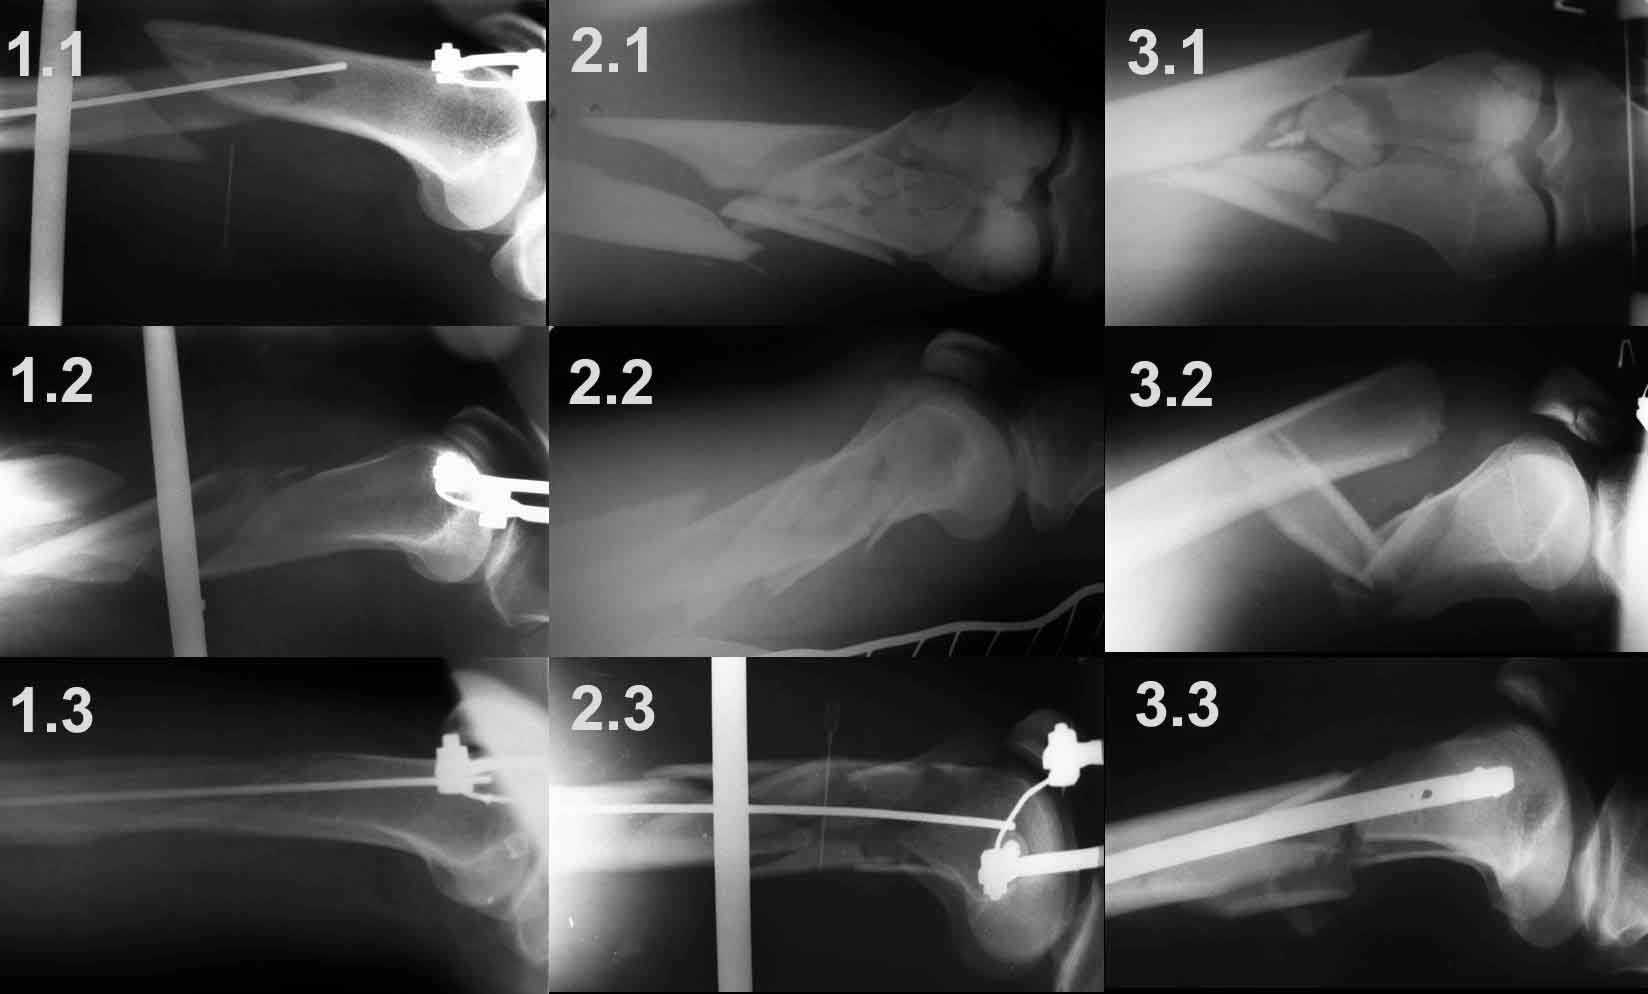

1. Открытый с дефектом кости 5 см оскольчатый внутрисуставной перелом дистального эпиметафиза бедренной кости. Величина дефекта установлена после сравнительных рентгенограмм обоих бёдер с линейкой. При поступлении выполнена ПХО раны, скелетное вытяжение за бугристость большеберцовой кости.

2. После долгих сомнений выполнена открытая репозиция перелома эпифиза бедренной кости, закрытый блокированный интрамедуллярный остеосинтез (к слову, оперативное вмешательство выполнено без применения ЭОПа). Предполагалась через 8 недель пластика костного дефекта спонгиозным аутотрансплантатом.

3. Снимок через 10 недель после операции. Имеется облаковидный регенерат. Решено от костной пластики воздержаться.

4. Через 6 месяцев имеем сросшийся перелом.

Безусловно, так бывает не всегда. Но, что касается показаний к костной пластике, такой вариант развития событий надо иметь ввиду.

1.1 – спица проведена сразу за передним кортикальным слоем дистального отломка, поэтому при дистракции появляется задний угол.

1.2 - спица проведена на линии середины диафиза бедренной кости, что привело к передней угловой деформации

1.3 - спица проведена в механически обоснованной точке (0,5 – 0,7 см дорсальнее передней поверхности кортикального слоя), что привело к репозиции костных отломков и ликвидации угловых деформаций.

2.1 -2.3 и 3.1 – 3.3 служат подтверждением того, что любую угловую деформацию при коротком дистальном отломке можно весьма просто устранить, правильно расположив спицу цуг-аппрата.